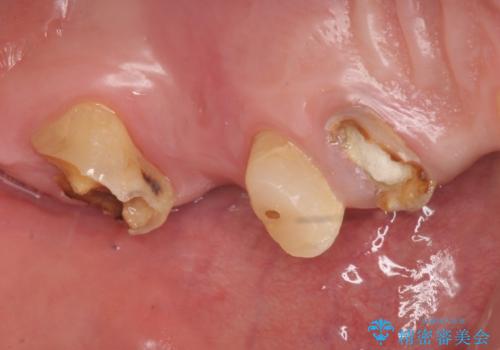

- 歯がない左側でものが咬めず、右側で咬むと歯が痛むので診て欲しいといらっしゃった方の症例です。

根尖病変が認められる歯は再根管治療を行い、歯根が破折していた左上4は抜歯しました。

インプラントは希望されなかったため、左側は1番から7番のロングスパンブリッジによる補綴を行いました。